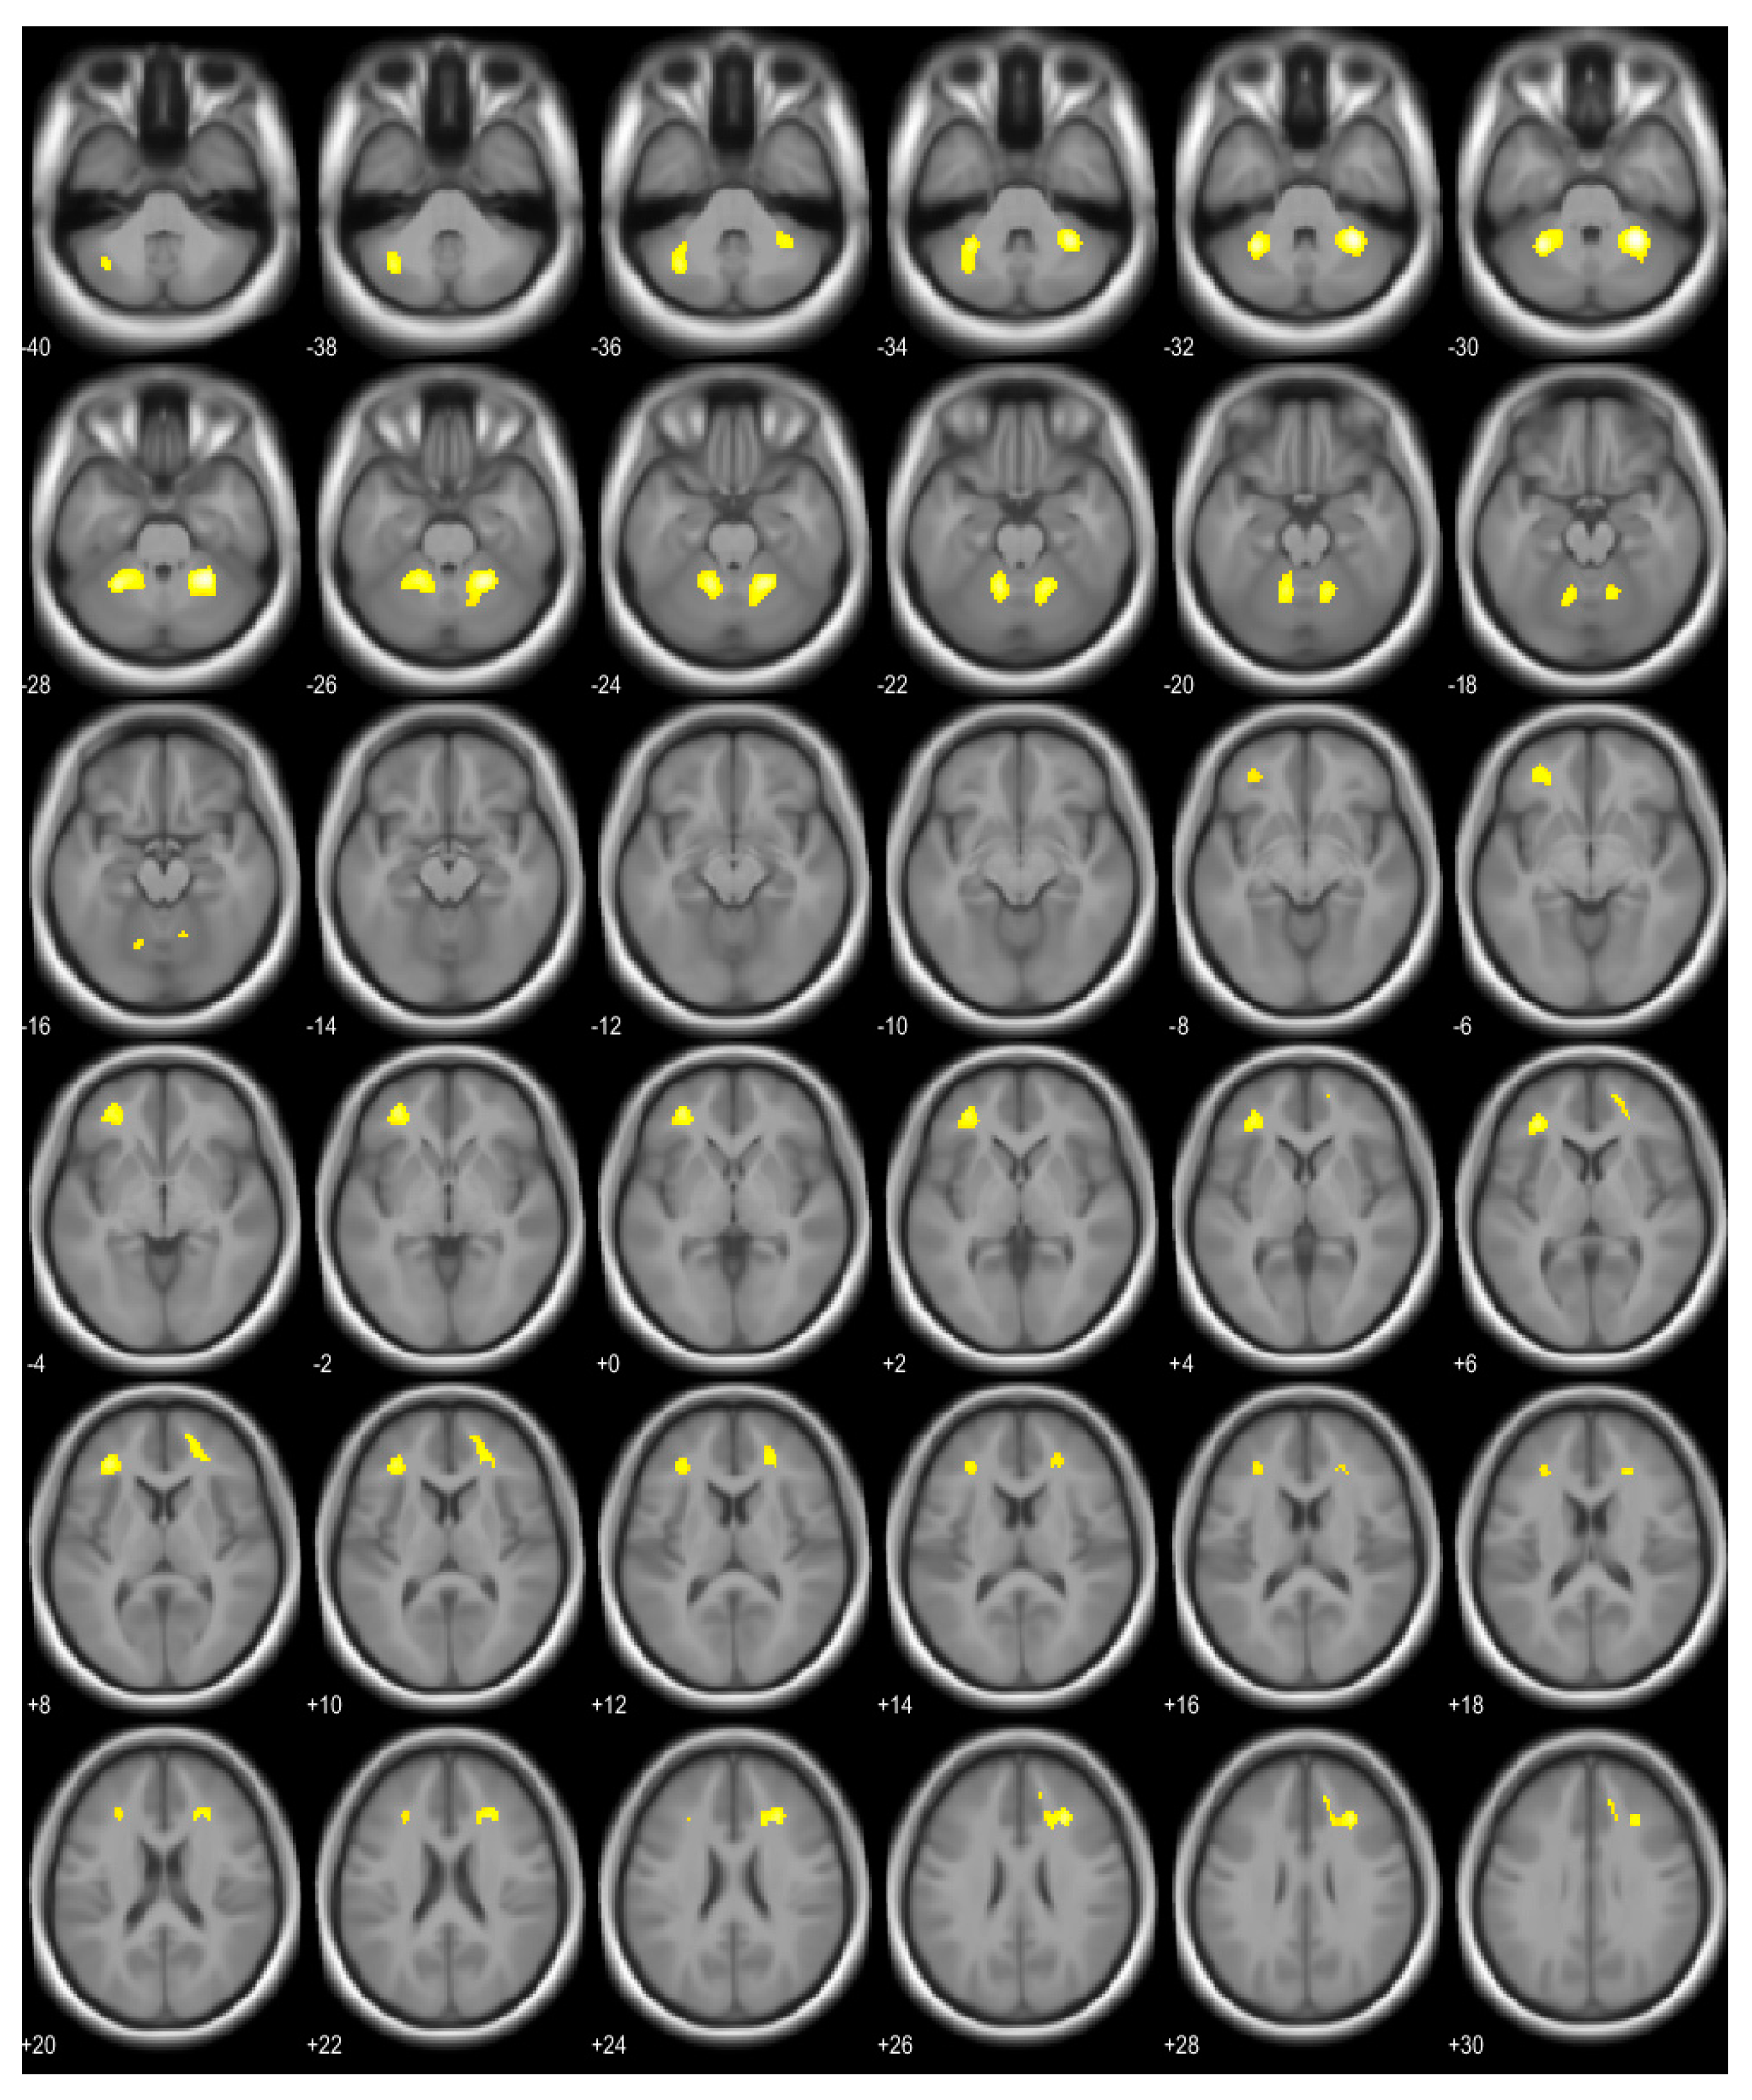

| Brain Area | Voxel | T | p (FWE Corrected) | Coordinates (x, y, z) |

|---|---|---|---|---|

| Right cerebellum, anterior lobe | 521 | 6.55 | <0.001 | 28, −48, −30 |

| Left cerebellum, anterior and posterior lobe | 522 | 6.19 | <0.001 | −30, −50, −30 |

| Right middle frontal gyrus, right cingulate gyrus, right anterior cingulate | 297 | 5.78 | <0.001 | 28, 30, 26 |

| Left middle frontal gyrus, sub-gyral area of left frontal lobe | 368 | 5.66 | <0.001 | −34, 38, 8 |